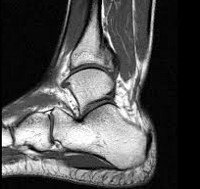

МРТ детского сустава используется в детской травматологии и ортопедии, ревматологии и онкологии для выявления травматических повреждений, воспалительных и опухолевых поражений суставов и окружающих мягких тканей. МРТ является единственным неинвазивным методом визуализации компонентов мягких тканей сустава: связок, сухожилий, хрящей, периартикулярных мешочков. Показания МРТ сустава для ребенка могут включать в себя травмы передней части, боль в проекции сустава, отек, покраснение, снижение подвижности В педиатрии МРТ исследует височно-нижнечелюстные суставы, плечи, локти, колени, бедра, лодыжки, ступни и кисти рук.

Обследование определенного анатомического региона имеет свои показания, определяемые детским специалистом. МРТ тазобедренных суставов ребенку проводится при подозрении на дисплазию (врожденный вывих бедра), артрит, перелом головки бедренной кости, остеомелит. С помощью МРТ коленного сустава у ребенка могут выявляться повреждения связок (передней и задней крестообразных, коллатеральных, собственной связки надколенника) и сухожилий, разрыв мениска, перелом надколенника, гонартроз, бурсит, артрит, болезнь Шляттера ). МРТ голеностопного сустава ребенку может назначаться при переломе голеностопа, разрыве связок. Исследование плечевого сустава ребенку с помощью МРТ проводится при привычном вывихе, разрыве капсулы или вращательной манжеты плеча, ущемлении сухожилий и нервов Проведение МРТ лучезапястного сустава ребенку показано при повреждении связок, переломе ладьевидной кости, отрыве шиловидного отростка локтевой кости МРТ височно-нижечелюстного сустава ребенку востребовано не только в травматологии (при переломах нижней челюсти и височной кости, излитии крови в полость сустава), но и в стоматологии (при планировании ортодонтического лечения).